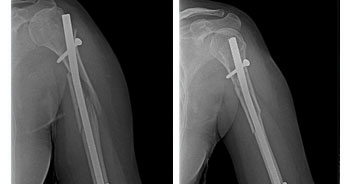

ADVANCED TRAUMA CARE

In any Trauma care center to receive and resuscitate the patient and to save life is our first priority. Saving the limb and other important organs is the next priority.

The hospital follows the principle of Triage, where by the patients are segregated by the surgeons as to have life threatening, limb threatening and other injuries depending on the type of injury, and are given treatment priority as the situation demands. To achieve this, a well-equipped intensive care unit and properly trained surgeons, anesthetists & Paramedical staffs are available, round the clock. Advance techniques in body warming, Sequential compression device, Alpha beds, and remote controlled ICU cots are available keeping the patients comfort in mind. Defibrillators, Ventilators, ABG analyzers, Cardio machine etc., are available to diagnose and prevent major complications.

• Trauma Surgery